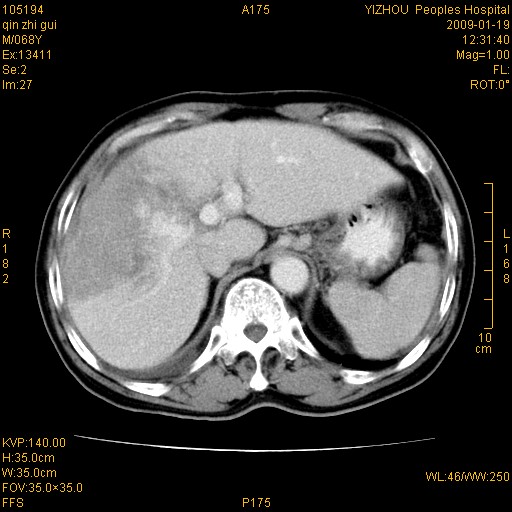

以下是引用随光逐影在2009-1-21 16:11:00的发言:[br]1)考虑肝右叶肝癌并肝静脉及门静脉瘤栓形成。2)肝硬化,少量腹水。3)胆囊炎。4)右侧少量胸腔积液。

病灶外缘凹凸不平,平扫低密度,增强动脉期有强化,门脉早显,静脉期及延期呈延迟强化,结合病史考虑右肝前叶巨块型肝癌可能性大,强化表现不除外胆管细胞癌